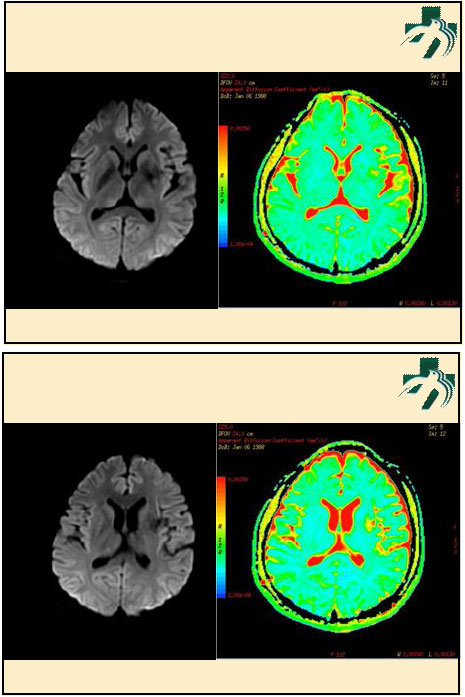

奴卡氏菌感染

第九期三博

读片会

病例之四

北京协和医院 提供

男性,22岁。自觉虫咬后皮疹、肢体麻木4月